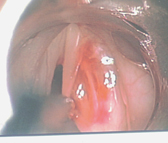

喉部顯微手術的過程其實非常簡單。首先,為了減少手術過程中的不適,患者需要接受短暫的全身麻醉。之後醫師會使用硬式的『喉直達鏡』(圖一),將會厭軟骨挑起並固定支撐後即可清楚的看到聲帶的全貌。跟一般門診使用的喉部內視鏡比起來(圖二,象牙白色直直的兩條即為聲帶),經過手術顯微鏡放大4-10倍之後,所有的聲帶病變均無所遁形,無論是聲帶表層常見的長繭(圖三,雙側聲帶長繭),或是聲帶息肉,都可以藉由特製的精細長柄器械,在顯微鏡下操作切除(圖四),以恢復聲帶平整的外觀。

圖二、正常聲帶外觀顯現兩條白色的聲帶,平穩而對稱。